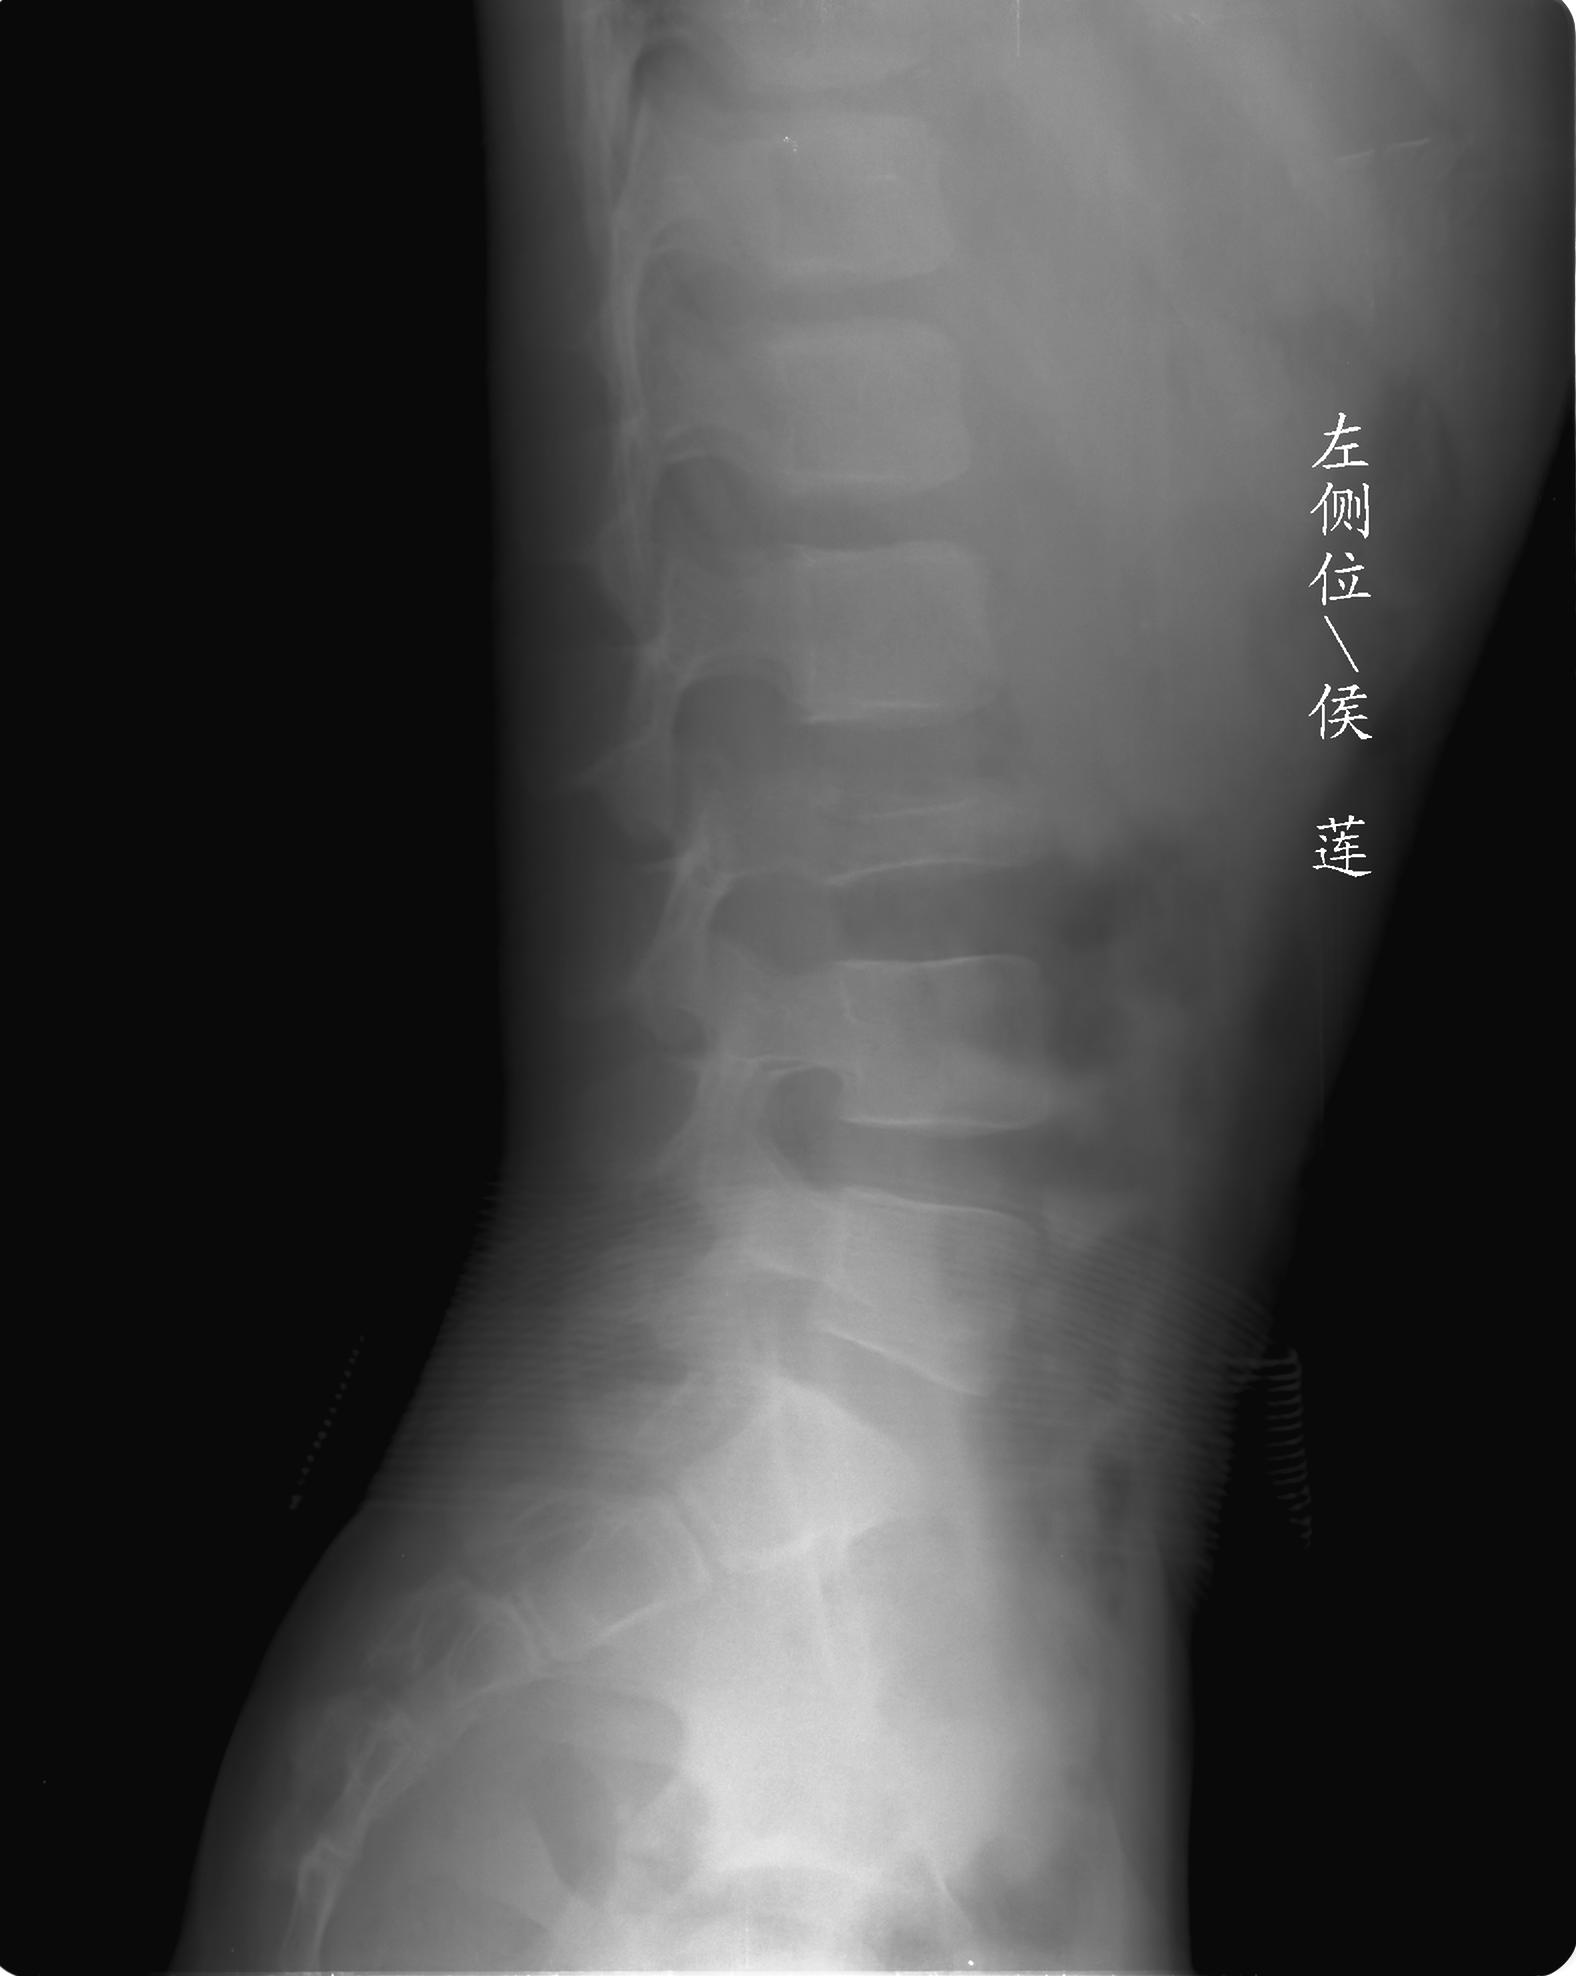

患儿女,11岁,因“腰痛,腰部活动受限10余天”入院。

10余天前,患儿无明诱因出现腰部疼痛,为持续性钝痛,以右侧为著,伴腰部活动受限,有发热,具体体温不详,无寒战、黄疸、盗汗、咳嗽,无尿频、尿急、肉眼血尿。

查:t37.8℃ bp100/60mmhg,心肺腹(-),腰部活动受限,腰椎旁有压痛,双下肢不肿,神经系统检查未见异常。

乍一看像是嗜酸性肉芽肿,但看到ct表现骨质破坏及软组织肿胀考虑结核可能性大,鉴别恶性肿瘤.

考虑l3嗜酸性肉芽肿。